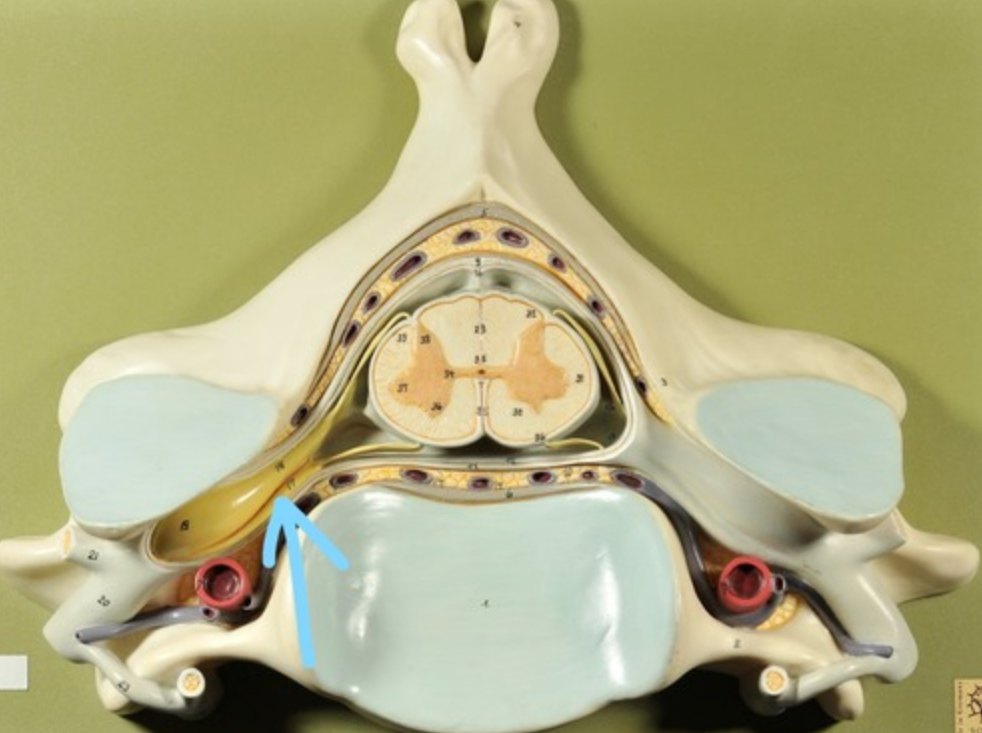

Spinal cord

Dura mater (outermost layer)

White matter of spinal cord

Gray matter of spinal cord

Ventral horns (of gray matter)

Lateral horns

Dorsal horns

Anterior columns of white matter

Lateral columns of white matter

Posterior columns of white matter

central canal of spinal cord

Pia matter

Subarachnoid space

Arachnoid matter

Subdural space (brown line)

Dura matter

Epidural space

Dorsal root ganglion

Dorsal root

Ventral root

Spinal nerve